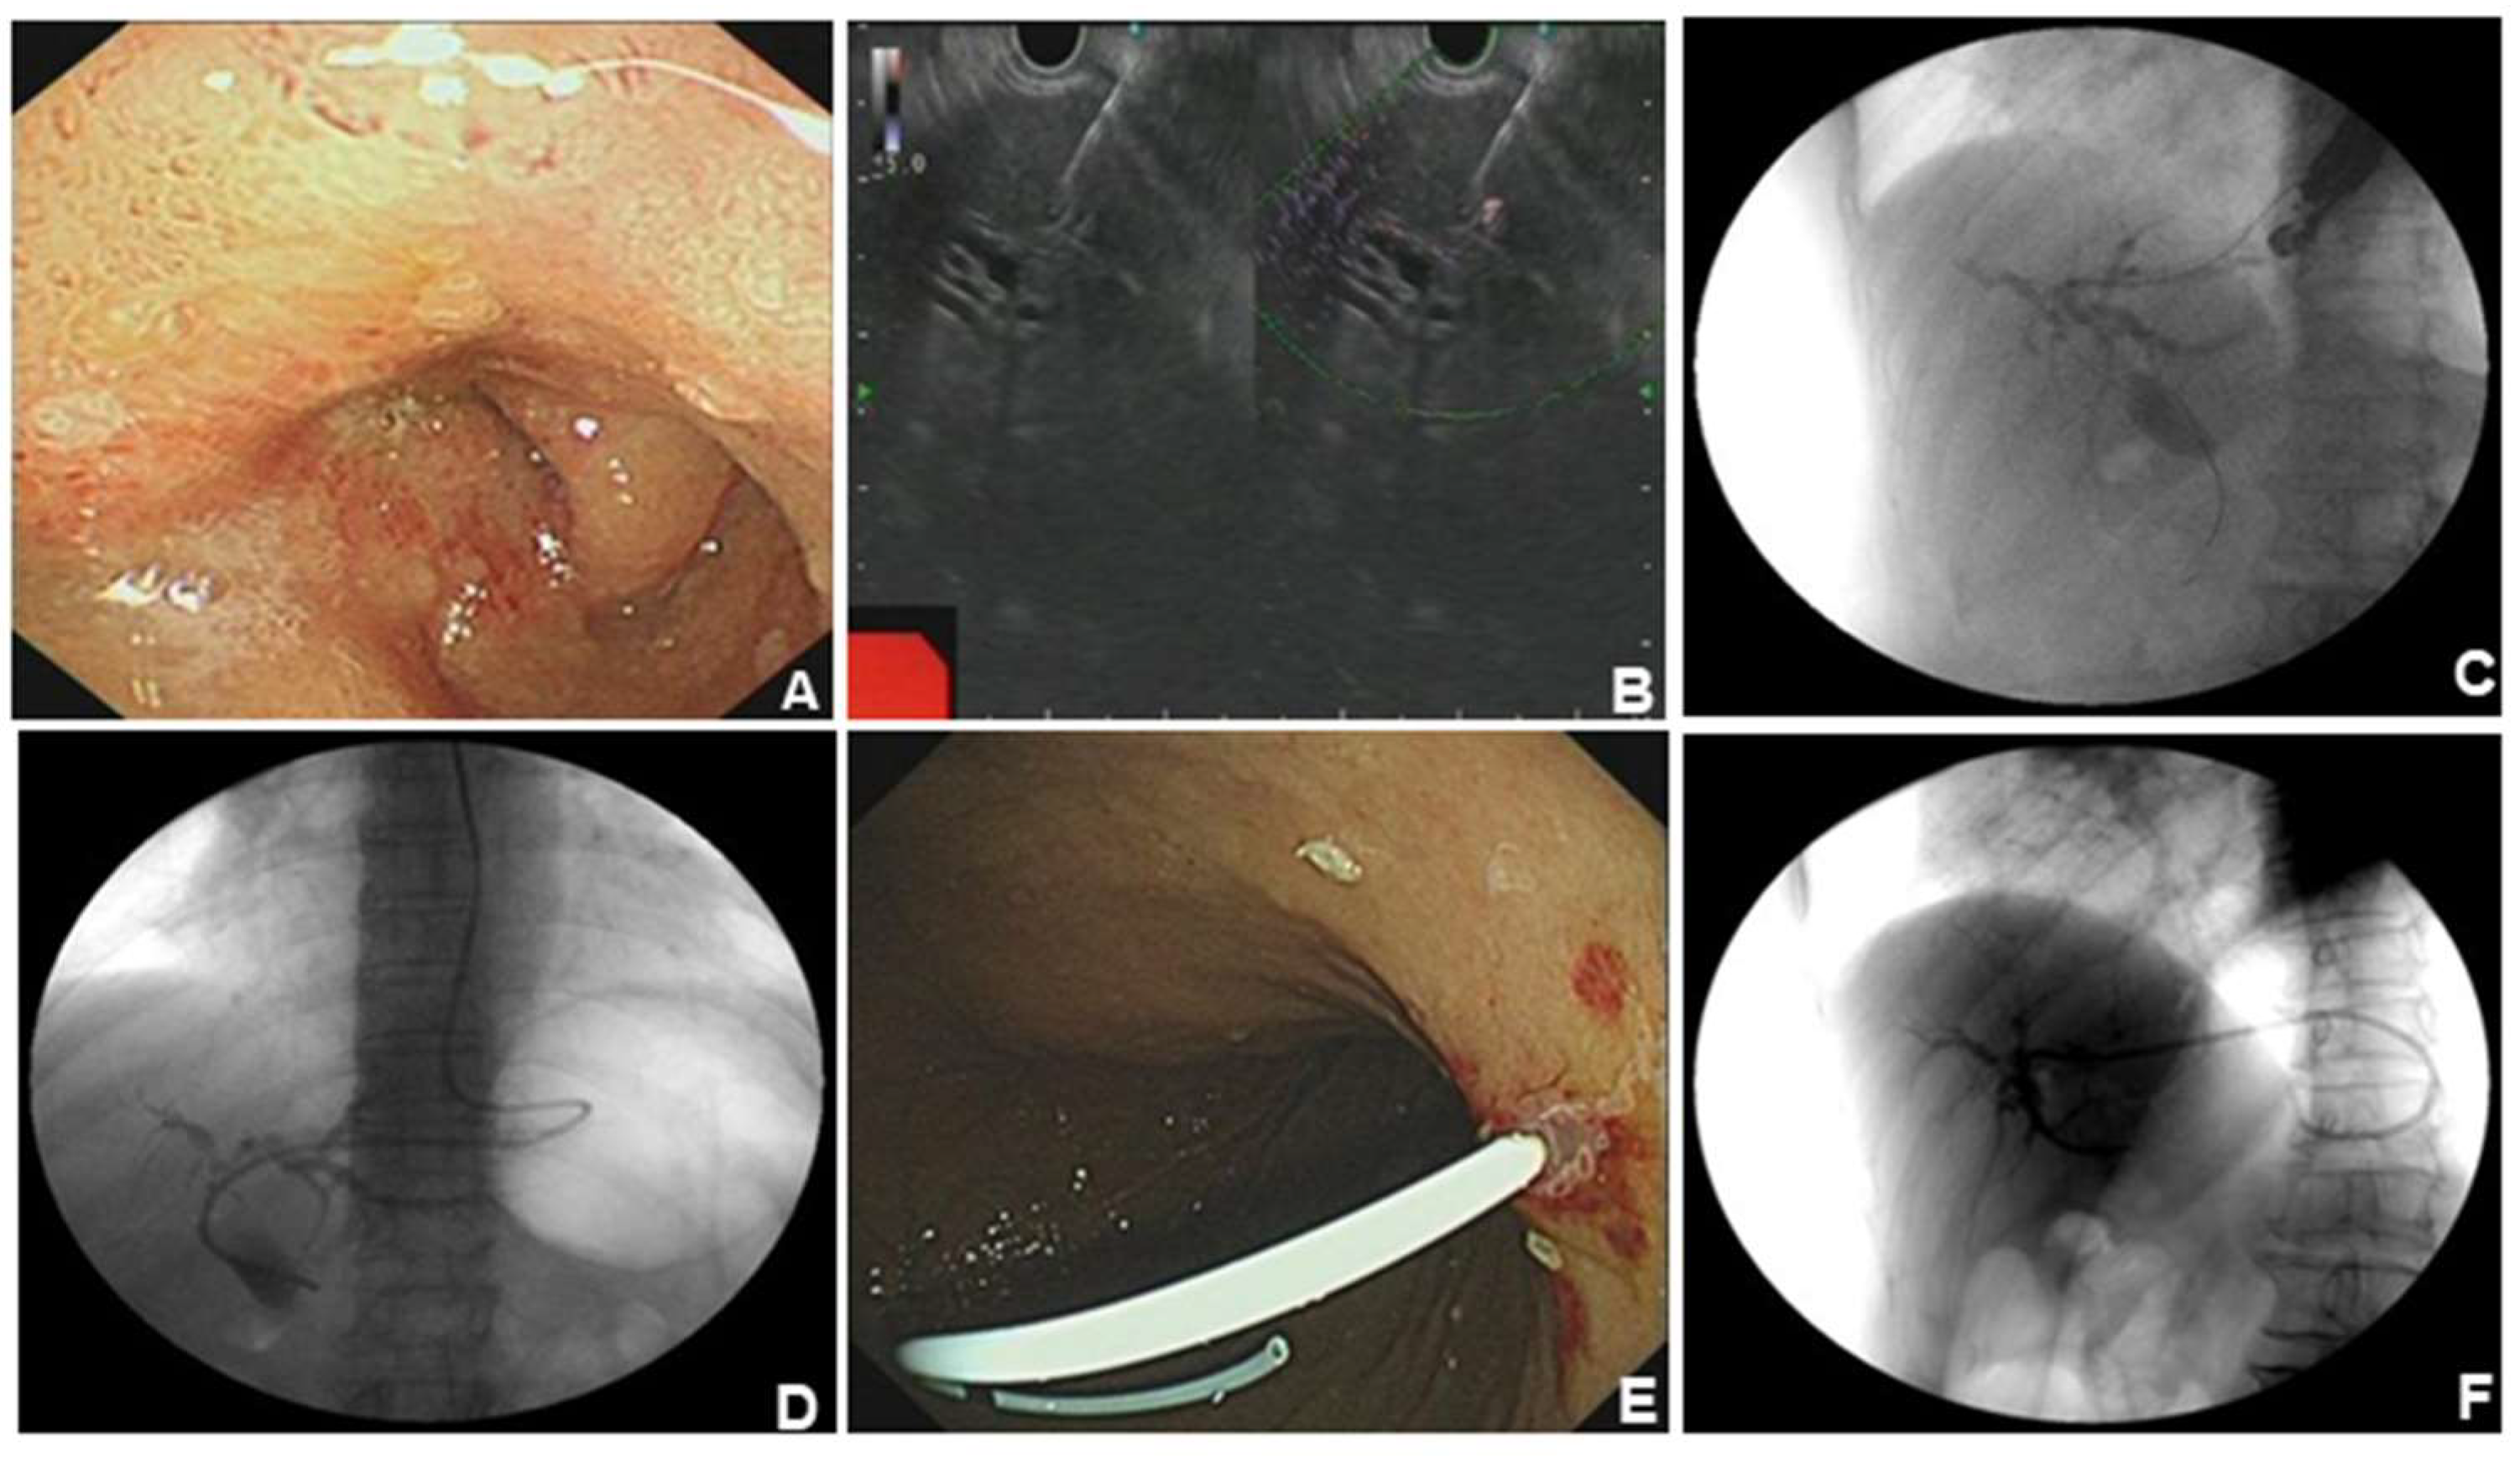

2] EUS-BD (including EUS-HGS and EUS-CDS) has appeared as a safe and efficacious alternative to PTCD or surgery when ERCP fails. A 76-year-old woman was admitted to our hospital with intermittent pain in the upper abdomen for more than 2 months, with scleral icterus for 1 week. Previous imaging and pathology suggested adenocarcinoma in the head of the pancreas, accompanied by dilatation of the common bile duct. The patient failed ERCP and received EUS-BD for relieving jaundice, and the whole operation was successful. (A). The patient had obstruction in the descending part of duodenal bulb and duodenal papilla was inaccessible for ERCP. (B). Ultrasonographic endoscopic puncture of the intrahepatic S2 segmental bile duct puncture. (C). Puncture had succeeded and contrast agent was injected to show the intrahepatic bile ducts. (D). Nasal bile duct placement for drainage. (E). Snipped nasal bile duct for stent drainage. (F). Stent position under X-ray.

ERCP remains the first-line method for accessing the bile duct. [